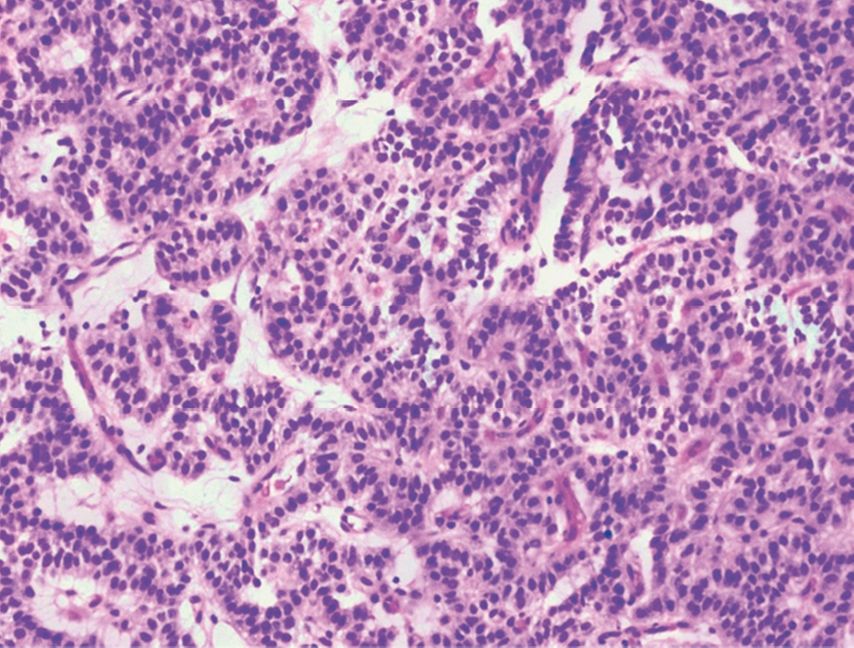

Der pathologische Befund der entnommenen Biopsien bestätigte die Verdachtsdiagnose eines typischen Karzinoid-Tumors (Abb. 4). Aus der laborchemischen Diagnostik sowie der klinischen Präsentation der Patientin ergab sich kein Hinweis auf ein begleitendes paraneoplastisches Syndrom.

Abb. 4: Histologie, HE-Färbung, 20-fach: typisches Karzinoid